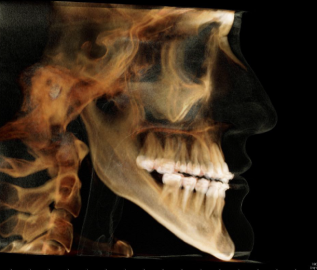

Nachher

Therapie:

Surgery First: Bignathe Umstellungsosteotomie (Minimalinvasive Le Fort I Osteotomie mit Vorverlagerung und simultaner Oberkieferdistraktion, gesonderte Spina Nasalis Osteotomie zur besseren Kontrolle von Oberlippenposition und -volumen, Anhebung der Nasenspitze, Unterkiefersegmentosteotomie 32-42 zur Vergrößerung der sagittalen Stufe (Dekompensation),

Kinnosteotomie, Side Wing Osteotomie mit Beckenkamminterponat)